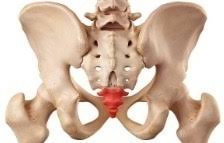

꼬리뼈 통증은 의학적으로 "미저골 통증(coccydynia)"이라고 하며, 척추의 최하단에 위치한 미저골(꼬리뼈)에 발생하는 통증입니다. 주로 앉을 때 통증이 심해지며, 장시간 앉는 생활이나 외상 이후 흔히 발생합니다. 통증은 단순한 불편감부터 심한 움직임 제한까지 다양하게 나타날 수 있으며, 여성에게서 비교적 더 많이 발생합니다.

1. 고관절 통증이란?고관절 통증은 허리 아래, 골반 주변, 사타구니 안쪽, 엉덩이 바깥쪽, 허벅지 앞뒤로 방사되는 통증을 포괄합니다. 고관절은 대퇴골과 골반을 연결하는 관절로 체중을 지탱하